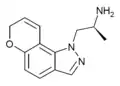

A number of related compounds are known, with a similar structure but having the indole core flipped and/or replaced with related cores such as indoline, indazole, benzothiophene, or benzofuran. These similarly are primarily active as agonists at the 5-HT2 family of serotonin receptors, with applications in the treatment of glaucoma, cluster headaches or as anorectics.

AL-38022A | (S)-2-(8,9-dihydro-7H-pyrano[2,3-g]indazol-1-yl)-1-methylethylamine | 478132-11-5 |

|